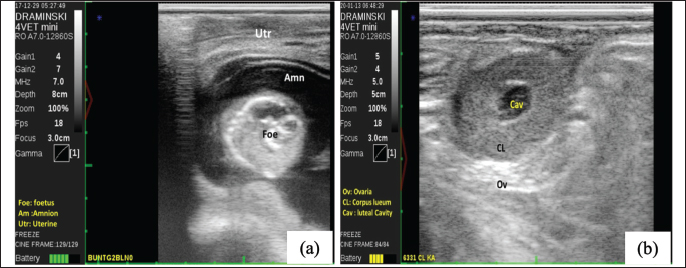

Fig. 2. Displaying pregnancy test using ultrasound (USG) at 60 days post-AI in FMD-infected cows (Foe: Foetus, Amn: amnion, Utr: Uterine) (a); depicting corpus luteum (CL) at normal oestrus cycle (Cav: luteal cavity, Ov: ovarium) (b).

The pregnancy test was performed at 60 days post artificial insemination with ultrasound to show the fetus and amnion (Fig. 2). Our study revealed that the S/C in FMD-infected cows post-treatment was 2.02 (Table 2). Moreover, CR and PR were 51 % and 85 % in FMD-infected cows post-treatment.